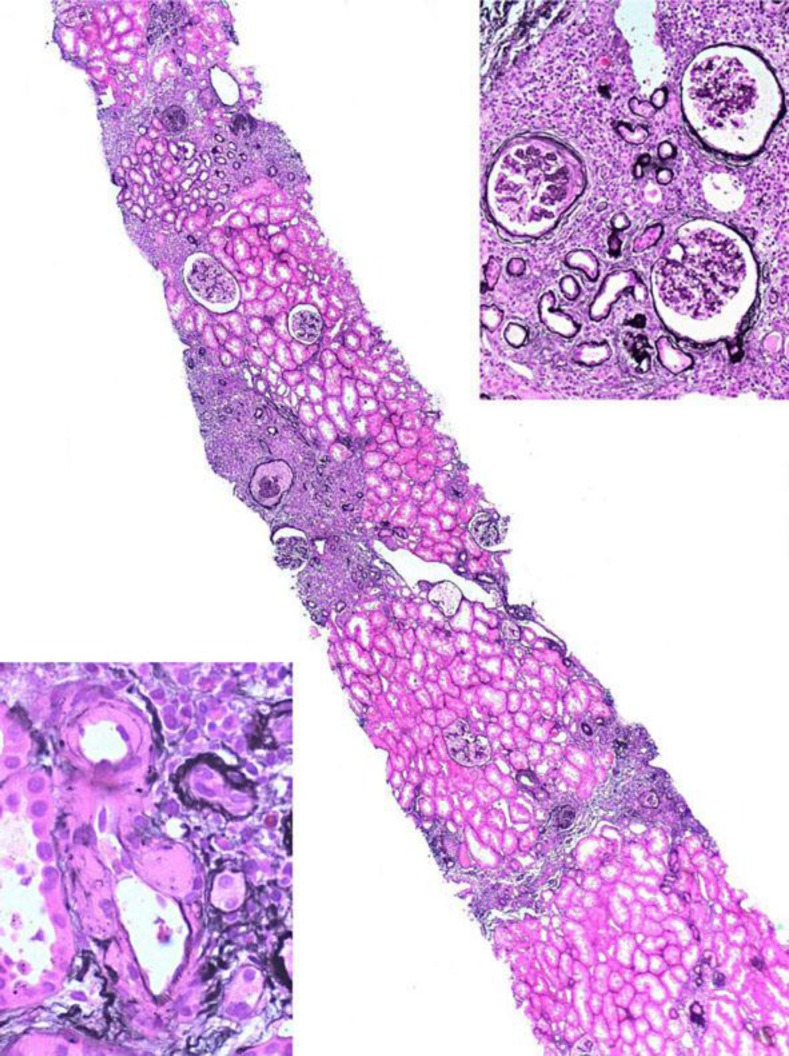

已知BK病毒(BKV)可引起儿童亚临床感染。病毒潜伏在人体内,主要存在于尿路上皮中。在开始免疫抑制治疗后,肾移植受者可发生再激活。BKV可引起出血性膀胱炎、输尿管狭窄和免疫功能低下患者的BKV肾病。此外,一些病例报告表明BKV感染与尿路癌的发展之间存在关联。到目前为止,已经在体外和动物模型中观察到BKV的致癌潜力;然而,其在人类中的致癌能力尚不清楚。我们报告一个59岁的病人谁发展为低分化肾细胞癌在她的肾移植,肺和腹部转移。手术切除同种异体移植物和停止免疫抑制治疗导致转移性疾病的完全解决。

BK virus (BKV) is known to cause subclinical infection in childhood. The virus remains latent in the human body, mainly in the urinary tract epithelium. After initiation of an immunosuppressive treatment, reactivation can occur in renal transplant recipients. BKV can cause hemorrhagic cystitis, ureteral stenosis and BKV nephropathy in immunocompromised patients. Furthermore, a number of case reports suggest an association between BKV infection and the development of urinary tract cancer. So far, an oncogenic potential of BKV has been observed in vitro and in animal models; however, its oncogenic capacity in humans remains unclear. We report the case of a 59-year-old patient who developed a poorly differentiated renal cell carcinoma in her renal allograft, with pulmonary and abdominal metastasis. Surgical removal of the allograft and cessation of the immunosuppressive therapy resulted in complete resolution of the metastatic disease.